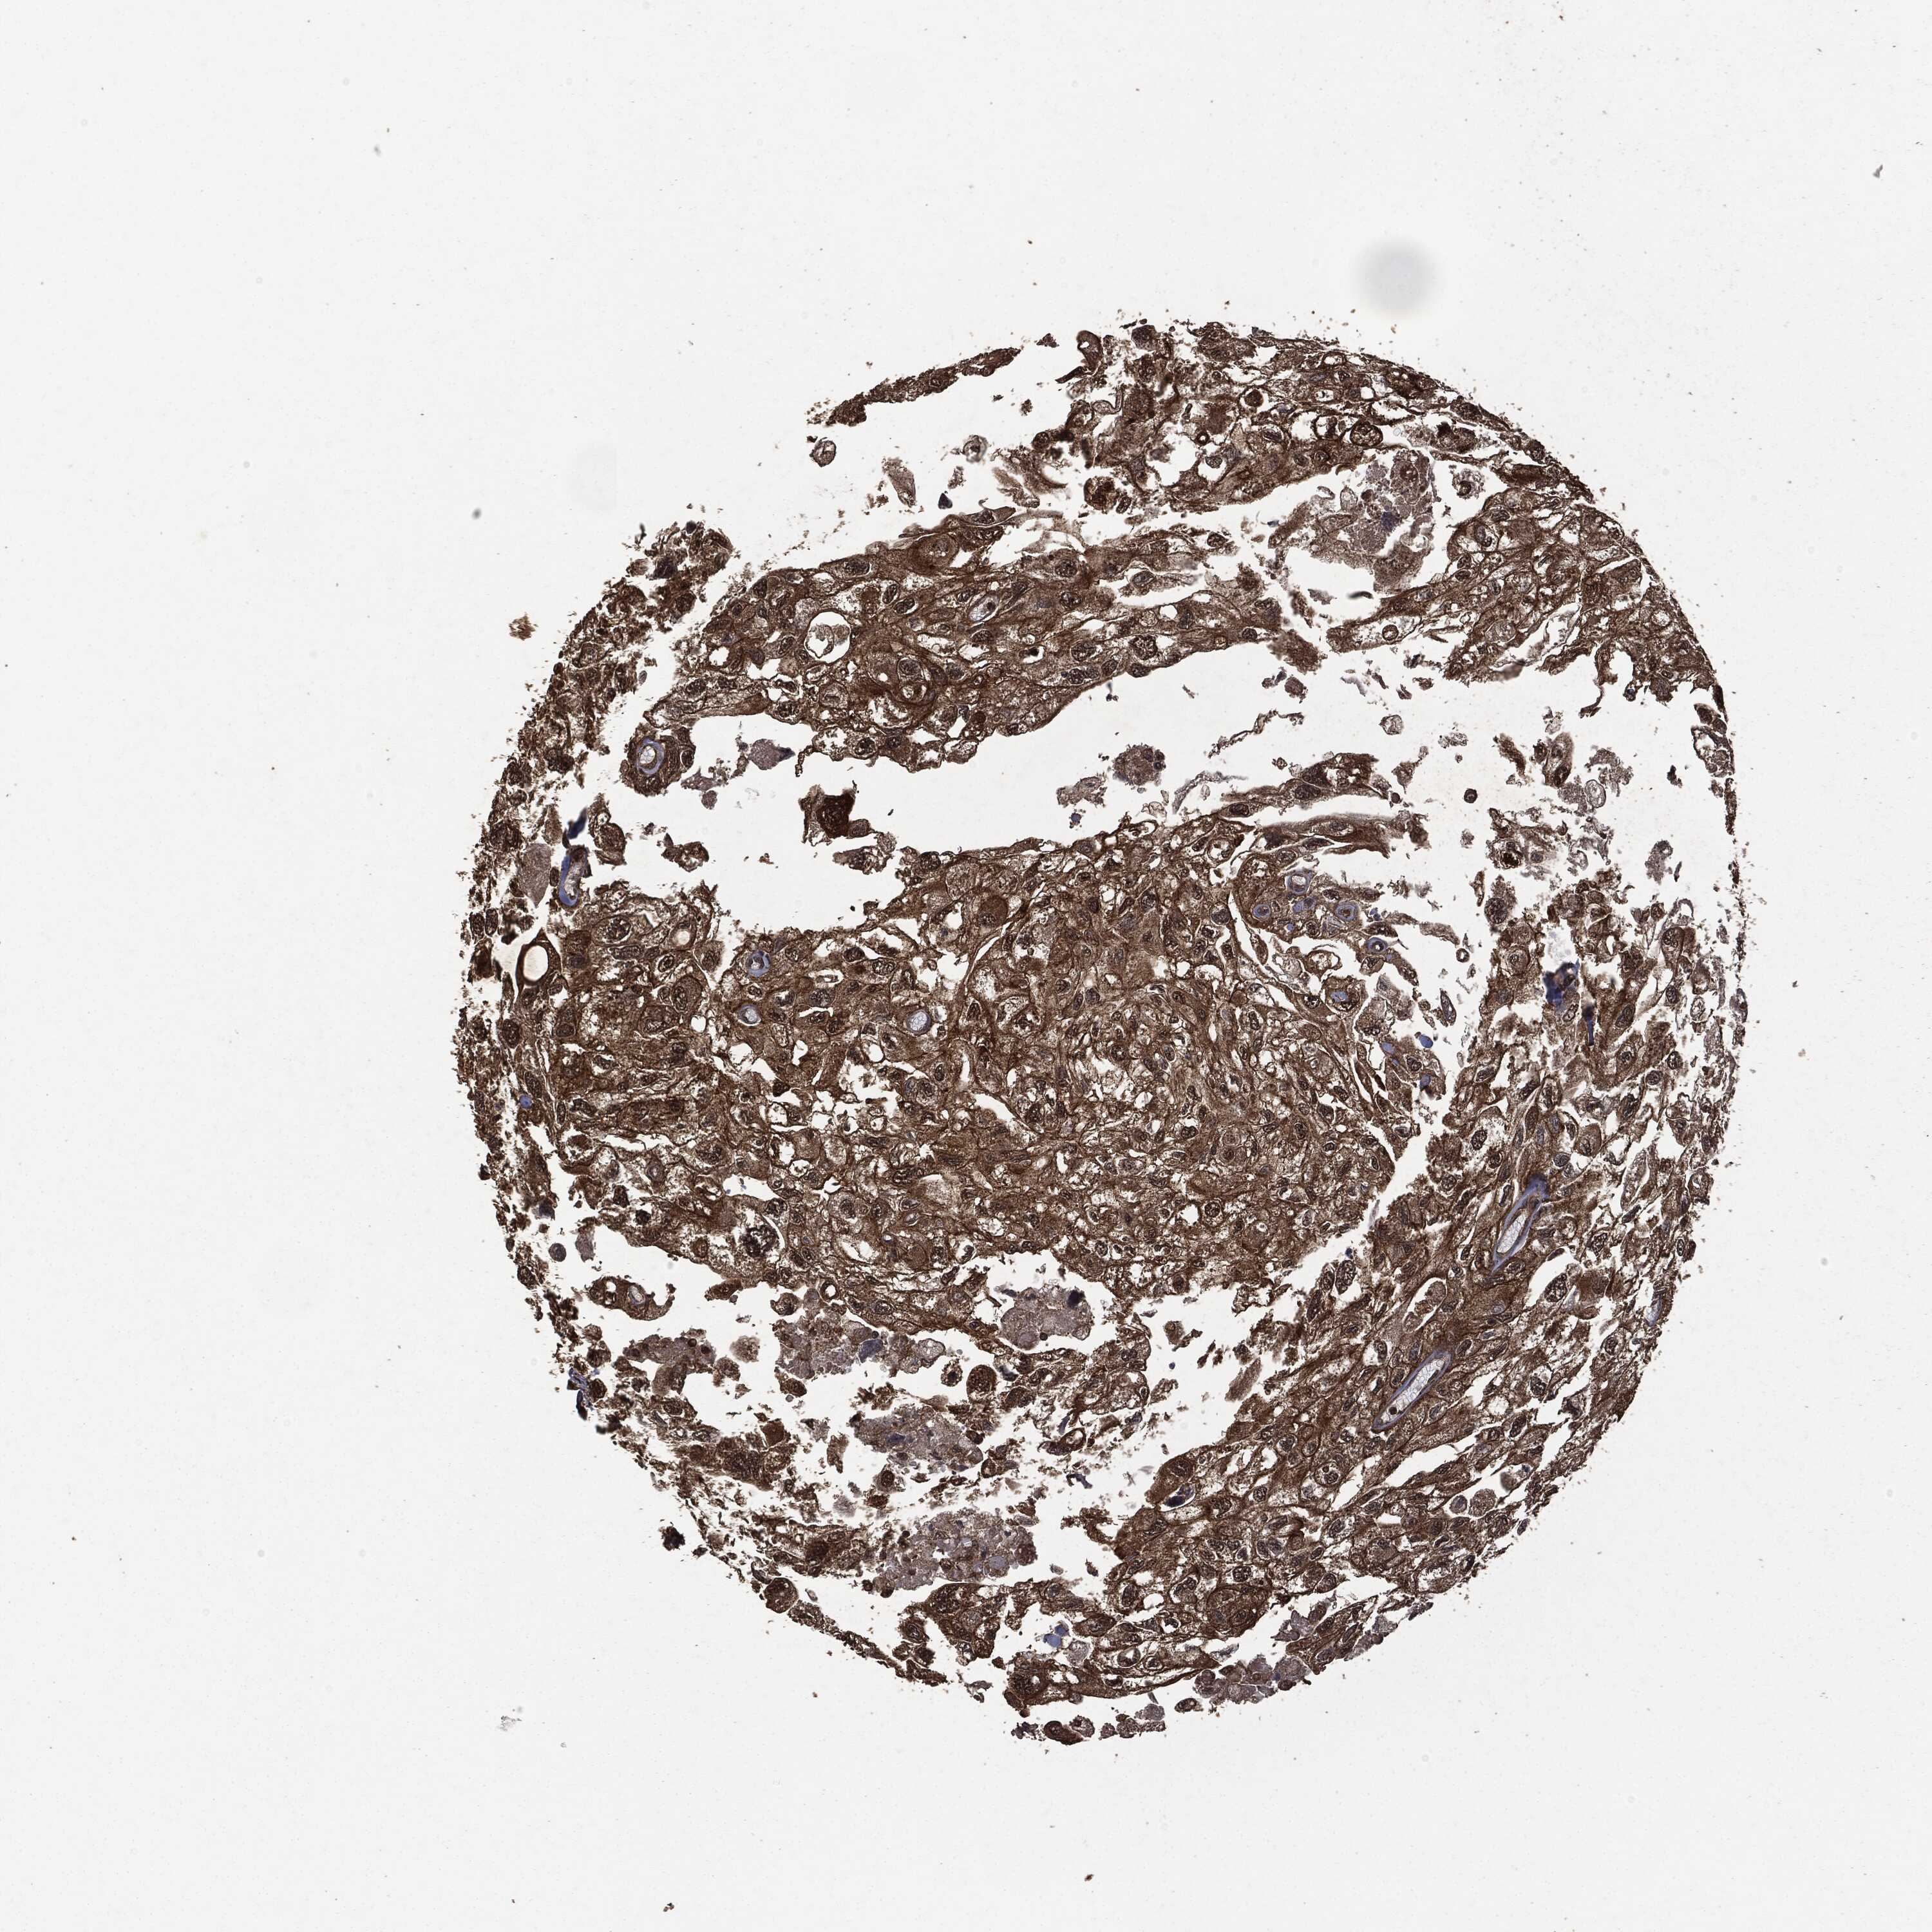

UROTHELIAL CANCER - Protein expressioni

A mouse-over function shows sample information and annotation data. Click on an image to view it in a full screen mode. Samples can be filtered based on level of antibody staining by selecting one or several of the following categories: high, medium, low and not detected. The assay and annotation is described here.

Note that samples used for immunohistochemistry by the Human Protein Atlas do not correspond to samples in the TCGA dataset.

Antibody stainingi

Antibody staining in the annotated cell types in the current human tissue is reported as not detected, low, medium, or high, based on conventional immunohistochemistry profiling in selected tissues. This score is based on the combination of the staining intensity and fraction of stained cells.

Each image is clickable and will lead to virtual microscopy that enables deeper exploration of all samples and also displays staining intensity scores, fraction scores and subcellular localization as well as patient and tissue information for each sample.

CAB002015

Urothelial carcinoma, High grade

Urothelial carcinoma, NOS

Urothelial carcinoma, Low grade

Adenocarcinoma, NOS